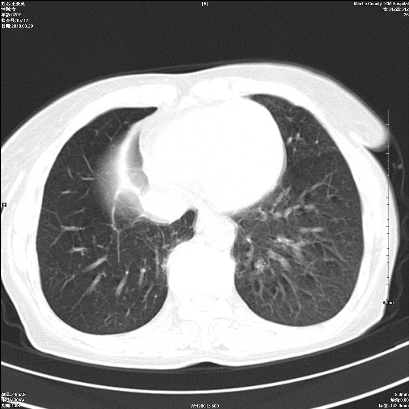

右肺上叶支气管开口阻塞,上叶呈不均匀致密影,右肺中下叶内见斑片状密度增高影,上叶见钙化点,纵隔内见钙化淋巴结,桶状胸,右下肺动脉增粗,残根征,意见:1.右肺中心性肺癌;2.右肺陈旧性结核;3.肺心病。

ct所见:右肺上叶肺不张,呈软组织密度影向肺门区聚拢,其内可见含气段支气管及细支气管影,病灶内尚可见钙化结节。右肺上叶支气管狭窄,段支气管壁可见钙化。右肺下叶背段、右肺中叶见不规则小片絮状影及纤维条索影,形态较僵硬。右肺中叶胸膜旁可见多个小结节影。纵膈内见钙化淋巴结。

分析:右侧胸廓及右肺体积缩小,说明病变时间比较长了,应该是有数年的时间了,如果是短期内出现的肺不张,只会引起纵膈向患侧移位,而不会引起胸廓的塌陷。不张的肺组织内可见含气支气管影,说明右肺上叶支气管没有完全中断,只是狭窄。右肺中叶、下叶散在不规则病灶,部分呈纤维化改变。纵膈内的淋巴结大部分钙化。因此,本例给我的感觉良性病变的可能是大。

结论:考虑右肺上叶支气管内膜结核合并右肺上叶肺不张;右肺中叶、下叶陈旧性肺结核改变。